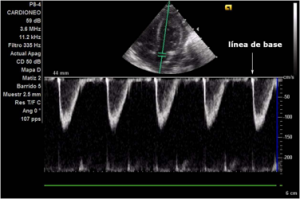

Para representar la señal Doppler, se usa una gráfica (ver figura) en la que las frecuencias Doppler o las velocidades se muestran en el eje vertical y el tiempo en el horizontal, mientras que la amplitud o potencia de cada componente del análisis se presenta en escala de grises

Si el flujo sanguíneo se acerca al transductor, se representa en la imagen por encima del eje horizontal (A); y si se aleja, por debajo del eje (B).